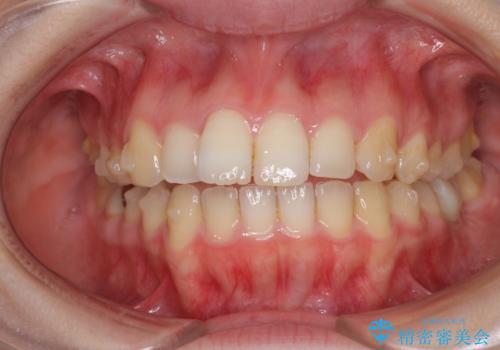

- 口の閉じにくさと割れてしまった奥歯を気にして来院された患者様です。

IPR(歯と歯の間を削る)と歯列全体の後方移動によって口元が引っ込むように設計し、インビザラインにより治療を行うこととしました。

上下正中がずれていたため、抜歯による矯正治療も検討しましたが、口元がそれほど突出していなかったため、非抜歯にて矯正することになりました。

その結果正中のズレは残りましたが、口を閉じたときの感覚や奥歯の咬み合わせには全く問題なく、患者様には大変満足していただきました。